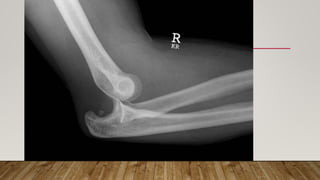

This document discusses radiology and the use of x-rays. It begins with an introduction to radiology and x-rays, noting their importance as the "father of medical investigations." It then discusses anatomy as seen on radiographs and whether x-rays are enough. The document goes on to compare gross views to radiological views, noting what each can and cannot show. It highlights important figures in the development of radiology, from x-rays to CT, MRI, and ultrasound. Specific anatomical structures visible on upper and lower limb x-rays are listed. The document concludes by discussing how pathologies appear on x-rays and the importance of clinical history and knowledge when interpreting radiological images.